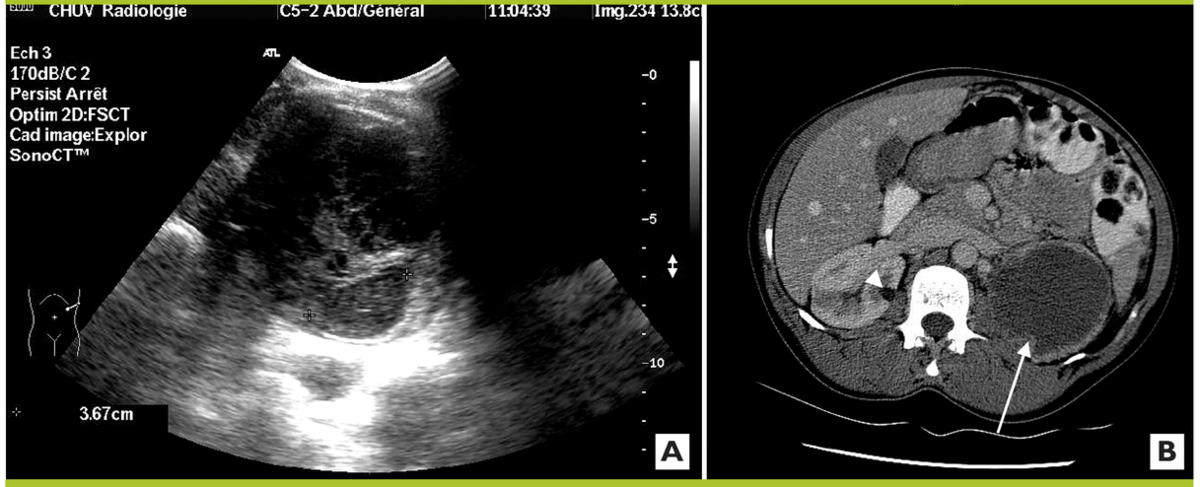

Quelle Attitude Lors De La Decouverte De Kystes Renaux